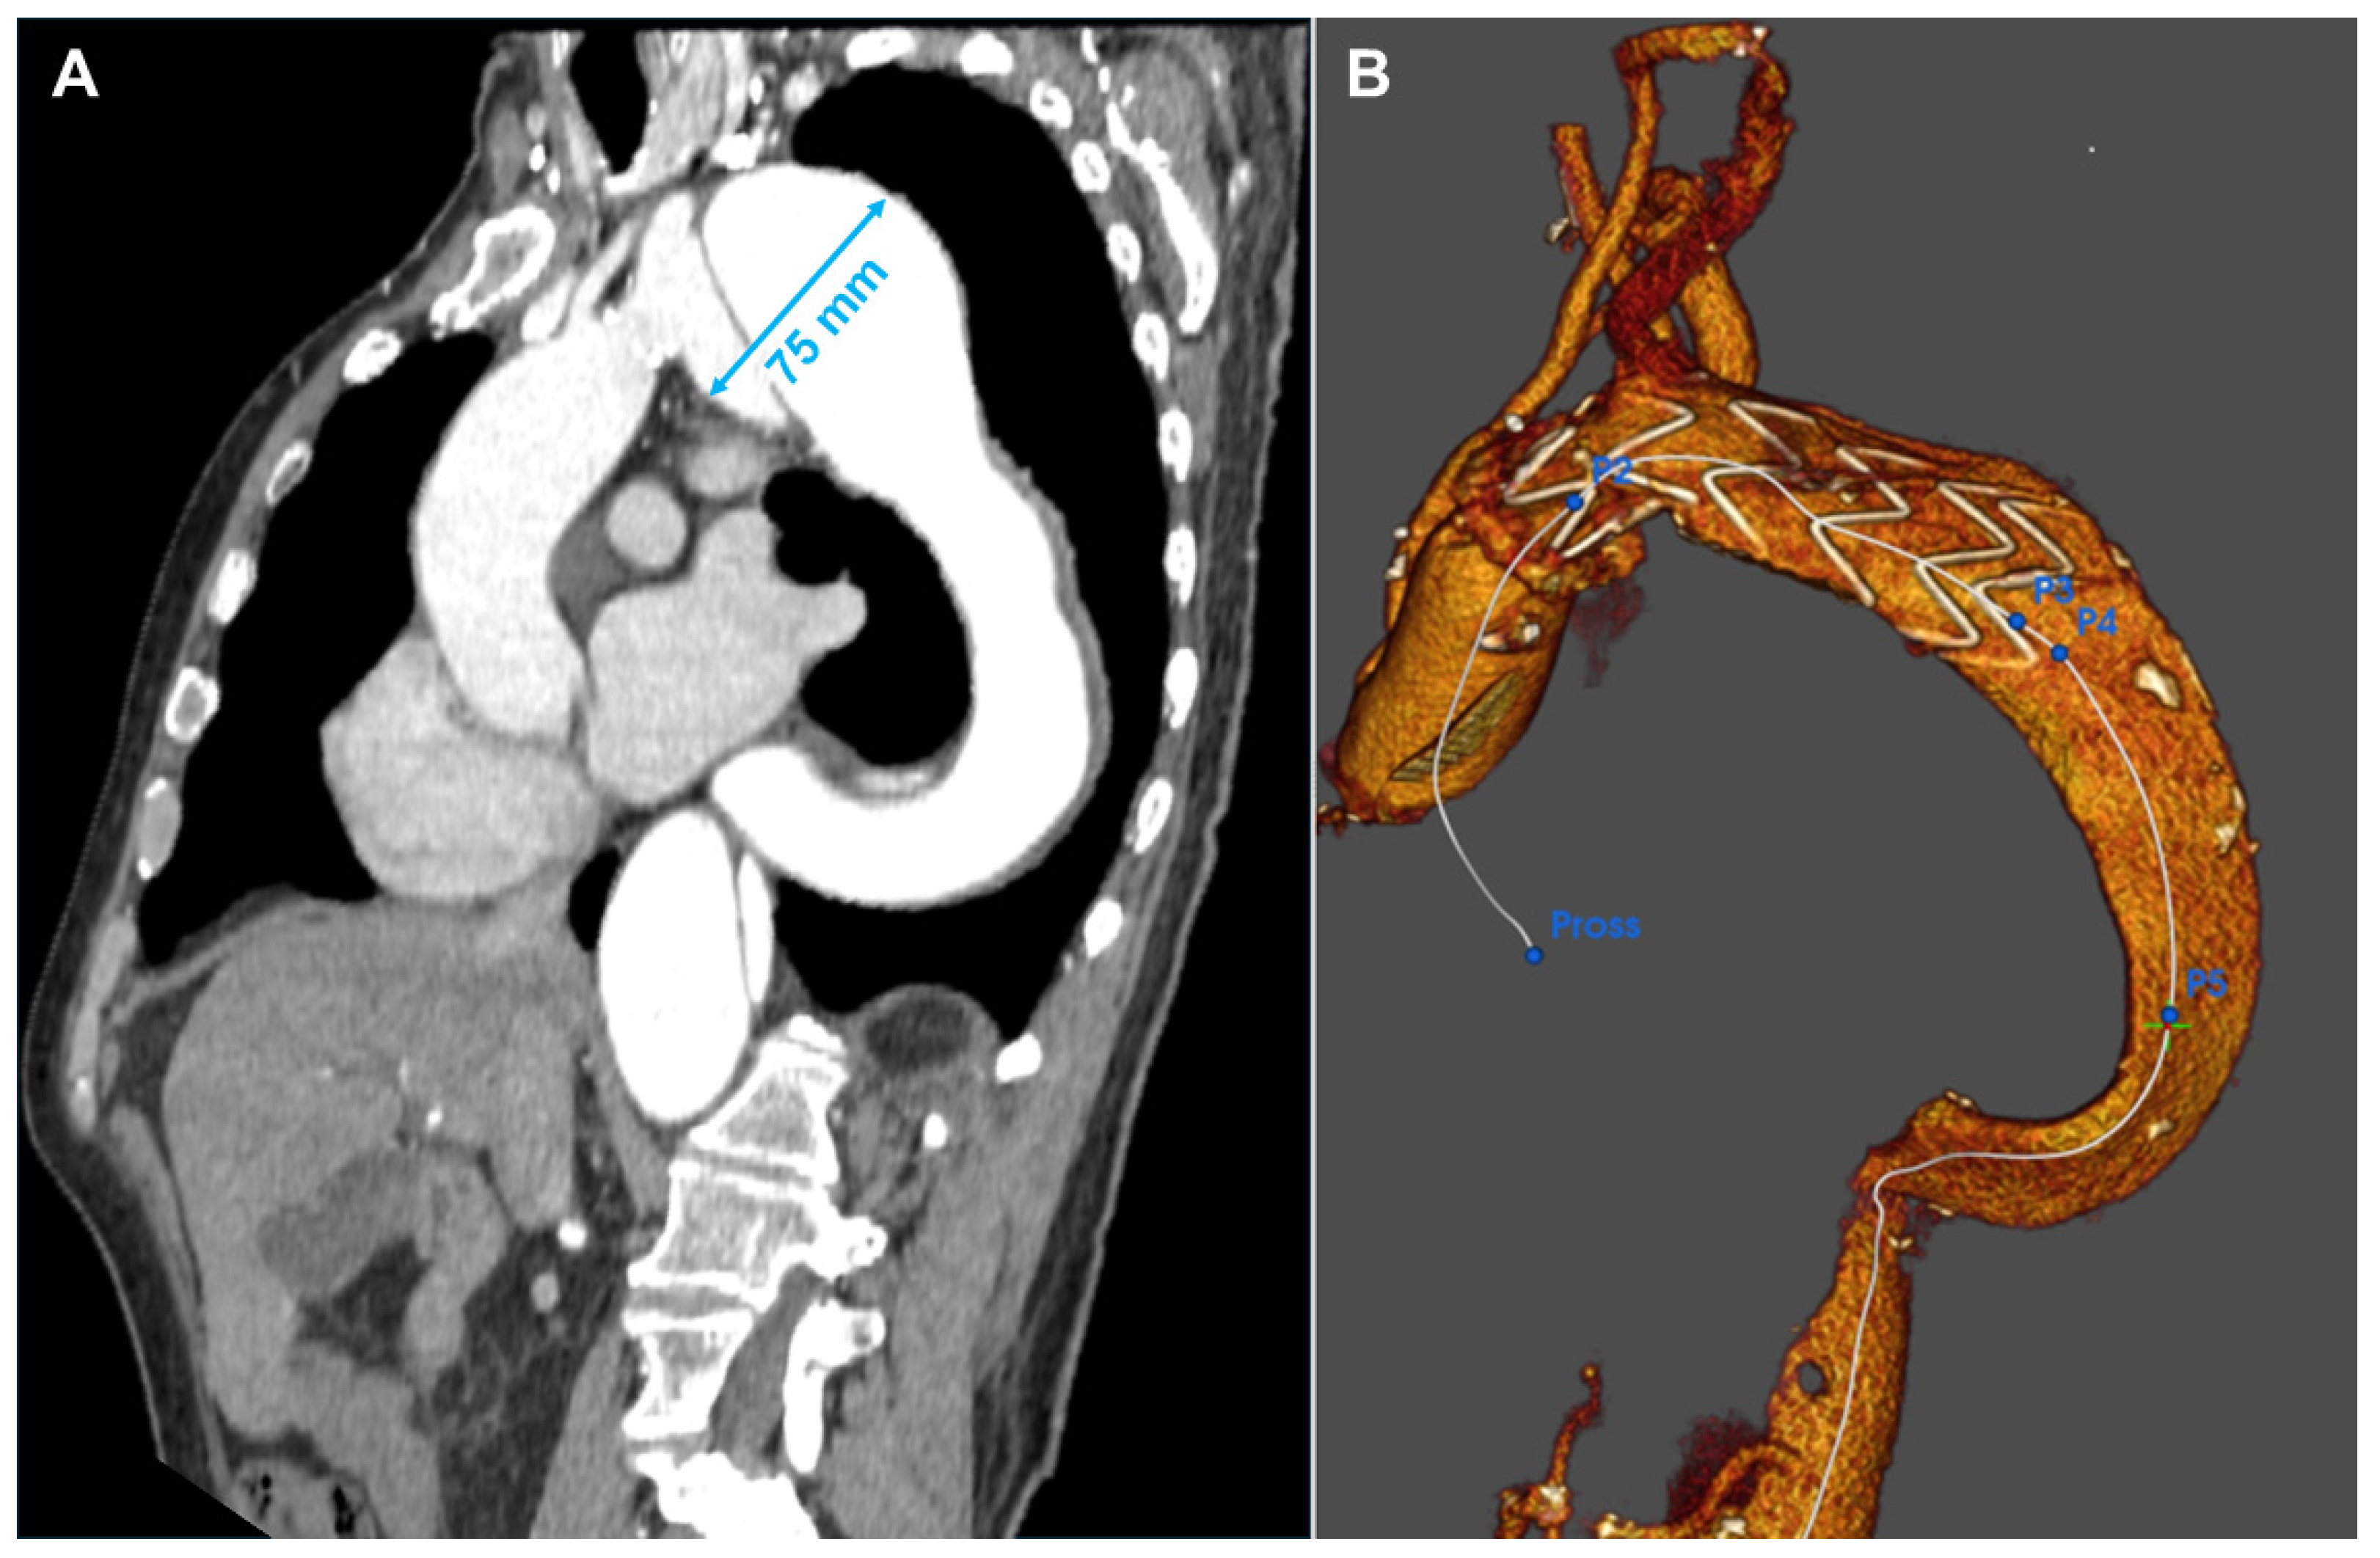

2.1. Patient 1

2.2. Patient 2

2.3. Patient 3

2.4. Patient 4

2.5. Patient 5